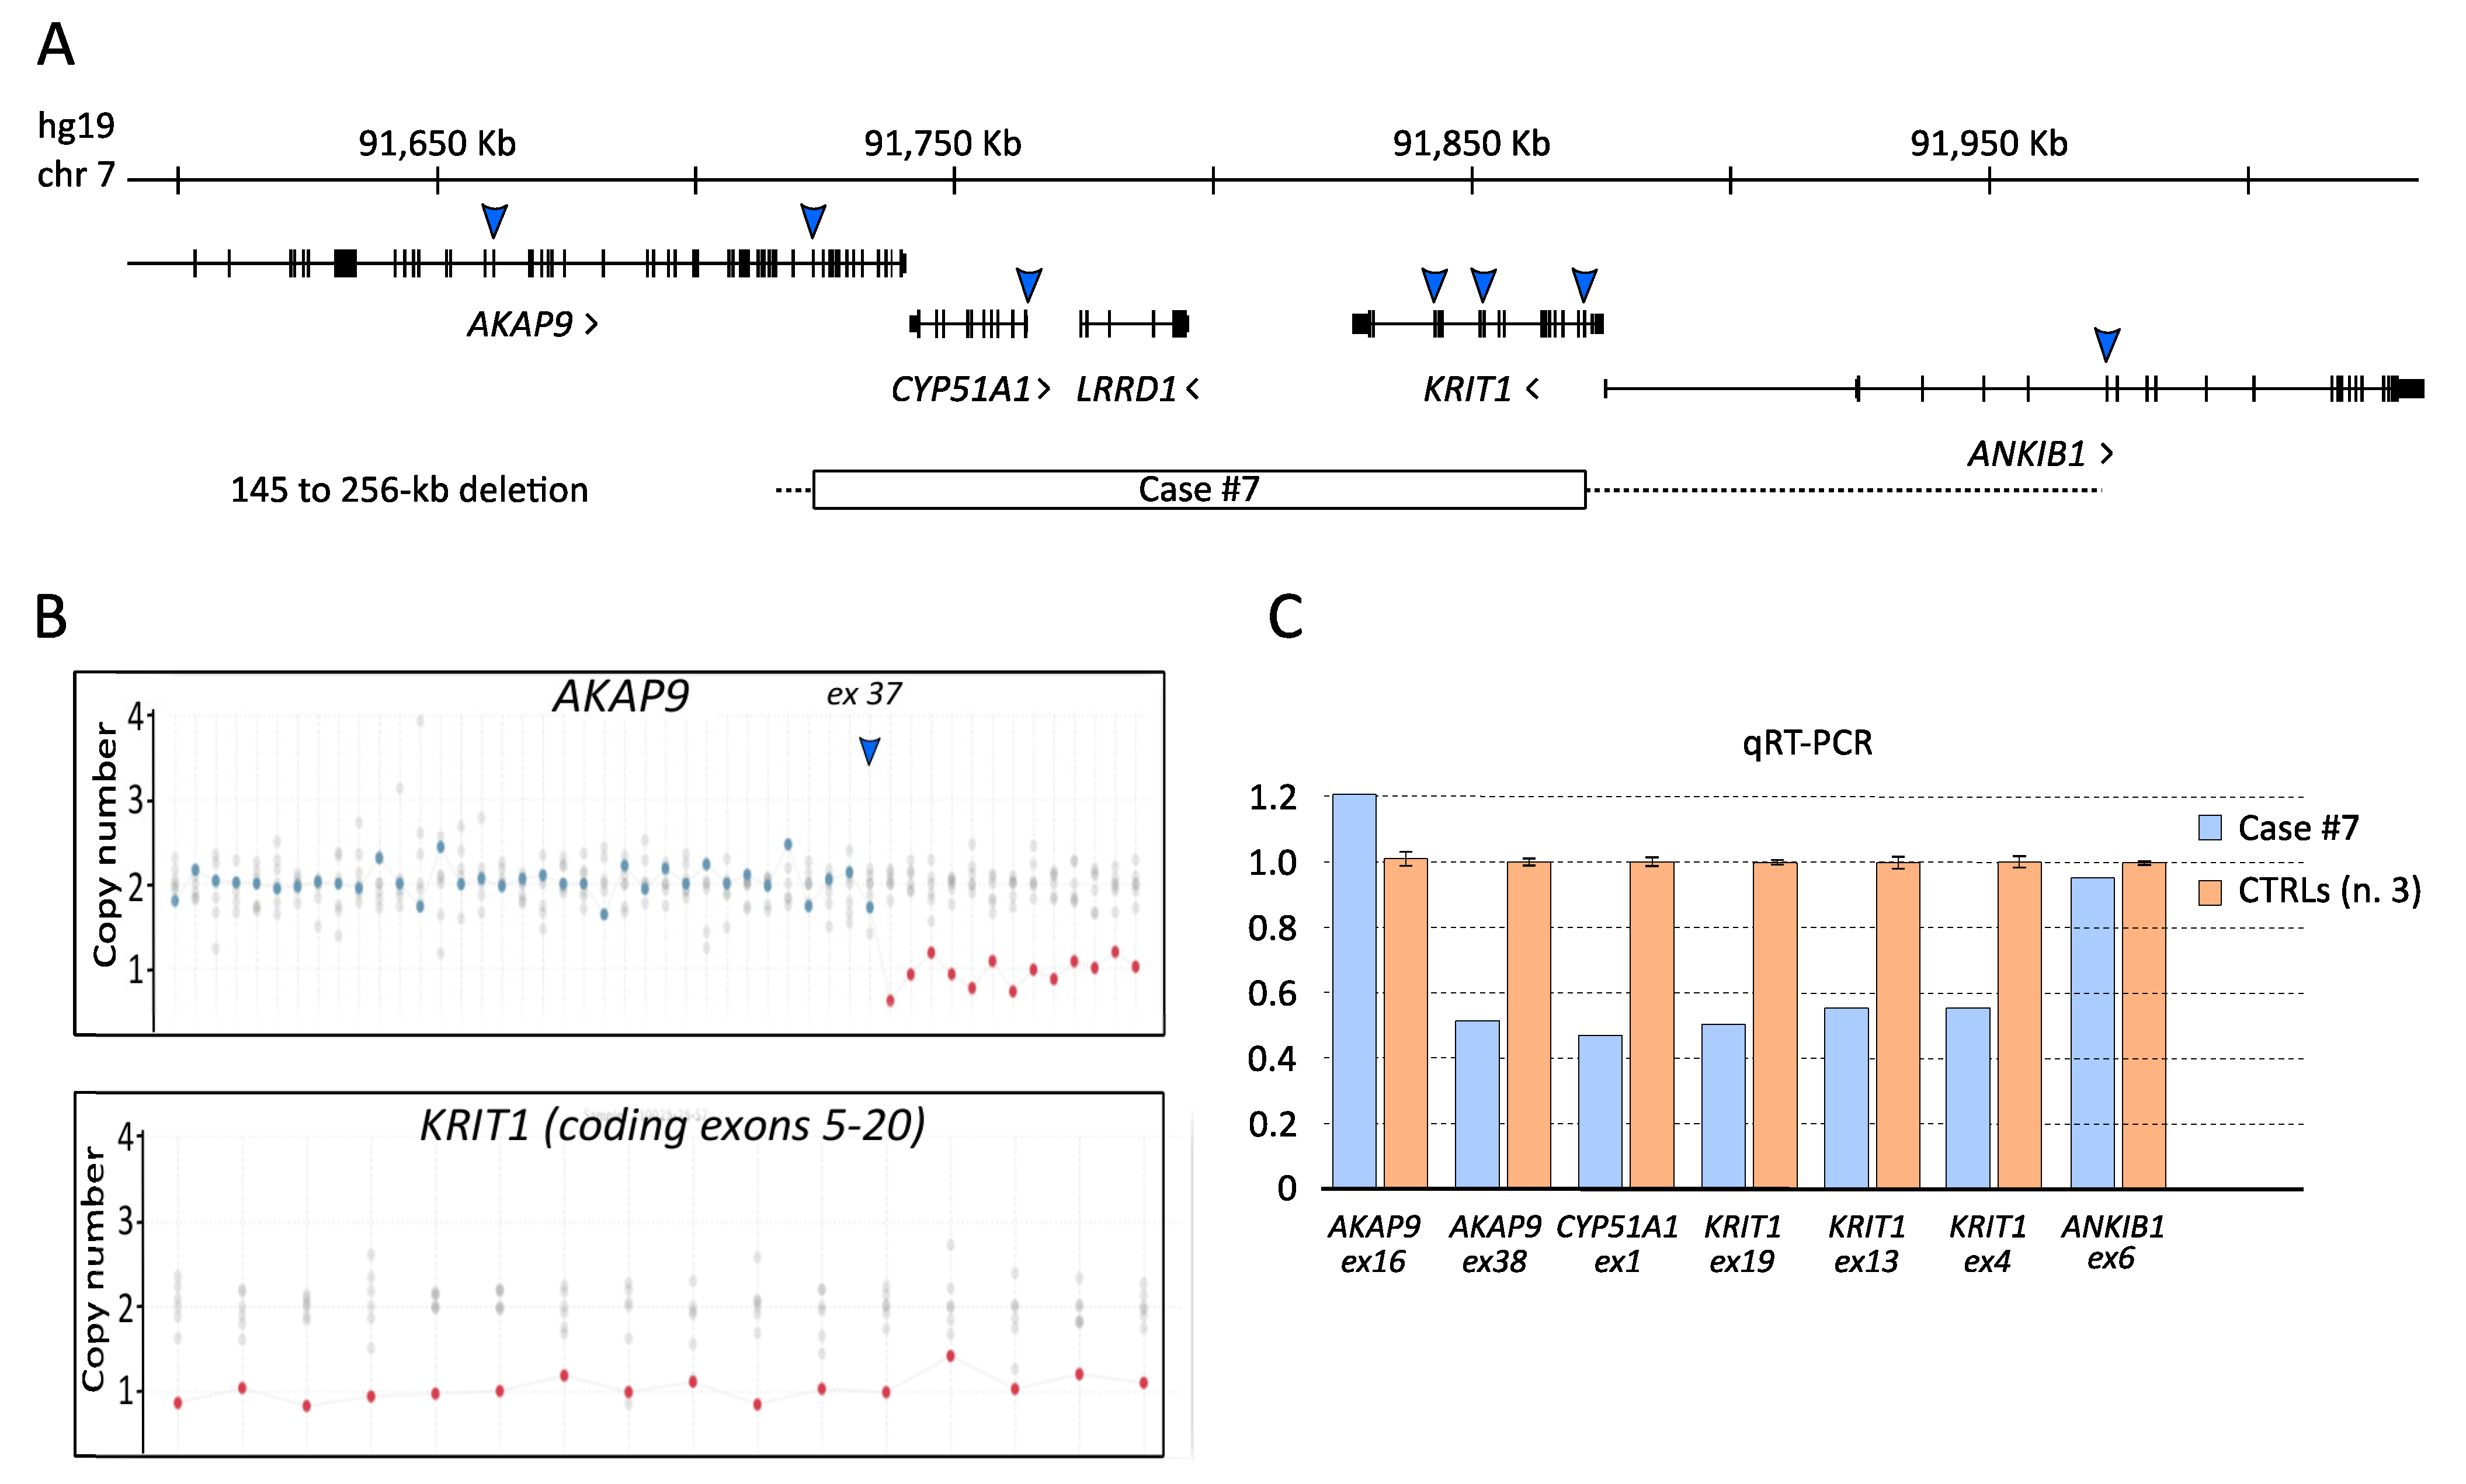

3.3. The KRIT1 c.1664C>T Variant Leads to Aberrant Exon Skipping and Segregates with CCM Disease